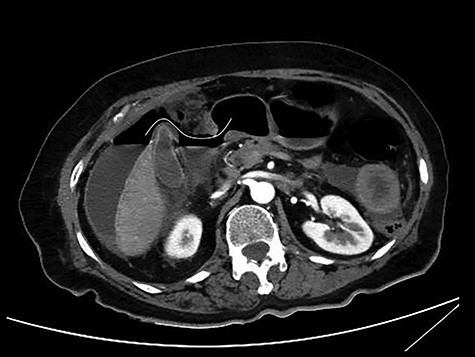

The patient was afebrile but hemodynamically unstable, with 115 bpm and a systolic pressure of 80 mmHg on presentation. Clinical examination revealed abdominal distension, diminished bowel sounds and severe tenderness with peritoneal signs in all of the abdominal quadrants. Her laboratory blood examination showed elevated number of neutrophils (7.77 K/μl), elevated C-reactive protein value (82.46 mg/dl) and decreased Na+ (119 mEq/l). After initial resuscitation, a computed tomography (CT) scan was performed. It showed free abdominal air and fluid in the peritoneal cavity, indicating an intestinal perforation (Figs 1–3).

CT scan without intravenous (iv) and oral (per os) contrast media administration: The disruption of lumen continuity at the level of duodenum bulb with presence of fluid (arrow head) and free air (arrows). There are also presence of free fluid in subdiaphragmatic space (dot) and edema in jejunum wall (open arrow). Contracted gallbladder is noted by star.

CT scan with iv and without per os contrast media administration: communication of free air with stomach (line).

CT multiplanar reconstruction (upper level, supine position) shows free air in continuity with intraluminal (duodenum) air. Notice the presence of free fluid in mesenteric pouches (stars), as well as encapsulated in the right paracolic gutter (arrows) and Douglas space (long arrow).